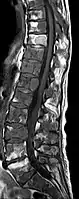

- Comparaison scanner/IRM pour des métastases ostéolytique d'un cancer du sein dans la colonne vertébrale

IRM natif avec pondération T1.

IRM sagittal natif avec pondération T1. On voit clairement l’extension jusqu'aux lames vertébrales.